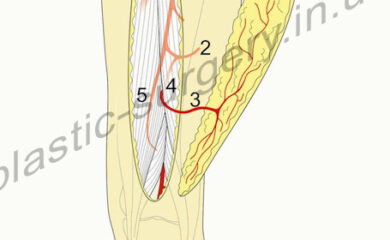

Ефективність передопераційної діагностики з використанням КТ-ангіографії при реконструктивних втручаннях на нижніх кінцівках

Авторы: С. В. Слєсаренко, П. О. Бадюл, С. О. Мунтян, К. С. Слєсаренко, О. О. Ковбаса Статья опубликована в журнале: Клін. хірургія. – 2016. – № …